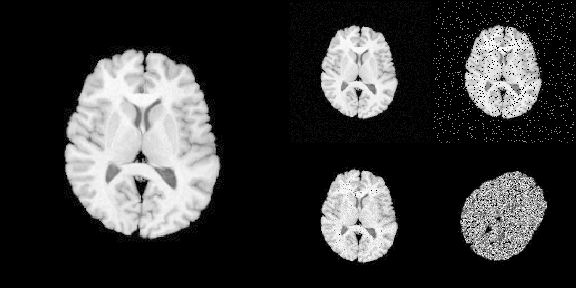

#> signature: (image, noise_model, noise_parameters)The following R code translates Python code into R:

# >>> img = ants.image_read(ants.get_ants_data('r16'))

img <- ants$image_read(ants$get_ants_data('r16'))

# >>> noise_image1 = ants.add_noise_to_image(img, 'additivegaussian', (0.0, 1.0))

noise_image1 <- ants$add_noise_to_image(

img, 'additivegaussian',

noise_parameters = tuple(0.0, 1.0)

)

# >>> noise_image2 = ants.add_noise_to_image(img, 'saltandpepper', (0.1, 0.0, 100.0))

noise_image2 <- ants$add_noise_to_image(

img, 'saltandpepper',

noise_parameters = tuple(0.1, 0.0, 100.0)

# >>> noise_image3 = ants.add_noise_to_image(img, 'shot', 1.0)

noise_image3 <- ants$add_noise_to_image(

img, 'shot',

noise_parameters = 1.0

# >>> noise_image4 = ants.add_noise_to_image(img, 'speckle', 1.0)

noise_image4 <- ants$add_noise_to_image(

img, 'speckle',

noise_image4 <- trans$apply_to_image(noise_image4)To load imaging data into R

# Use [] to convert ANTsImage into R array

is.array(img[])

#> [1] TRUE

# plot via R

layout(matrix(c(1,1,2,3,1,1,4,5), nrow = 2, byrow = TRUE))

par(mar = c(0.1, 0.1, 0.1, 0.1), bg = "black", fg = "white")

pal <- grDevices::gray.colors(256, start = 0, end = 1)

image(img[], asp = 1, axes = FALSE,

col = pal, zlim = c(0, 255), ylim = c(1, 0))

image(noise_image1[], asp = 1, axes = FALSE,

image(noise_image2[], asp = 1, axes = FALSE,

image(noise_image3[], asp = 1, axes = FALSE,

image(noise_image4[], asp = 1, axes = FALSE,